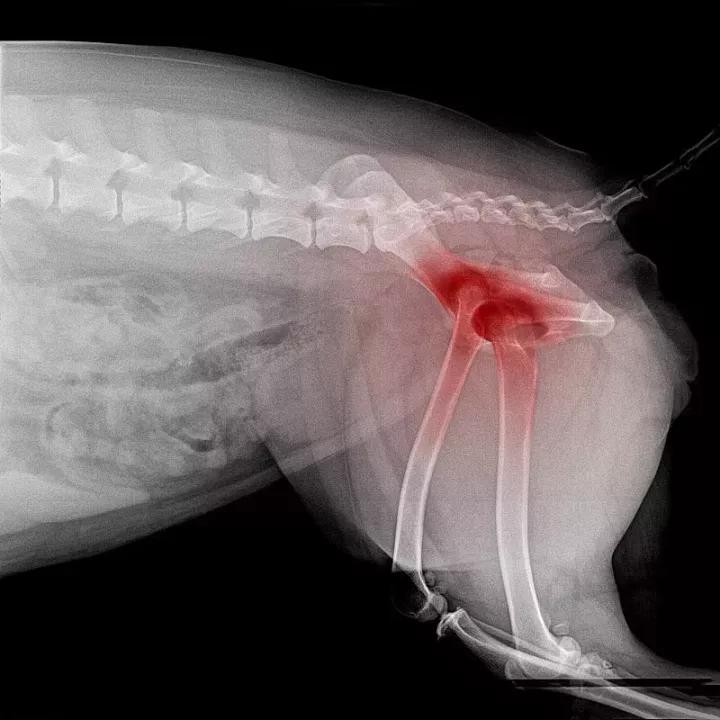

1、评估咬伤程度

医生需要对伤口咬伤程度进行判断,看是否需要缝合。如果不需要缝合,伤口会结痂并在一周之后开始脱落,露出下面的新生组织。每天检查结痂面是否干燥、是否有流脓出现。

用棉签蘸生理盐水擦洗伤口有助于保持伤口清洁并且减少感染几率。如果伤口开始肿胀,有脓液从伤口里流出,请立即去医院处理。

2、缝合伤口

超过1.5厘米的伤口可能需要缝合,这种情况通常需要在镇静或局部麻醉的情况下进行;狗狗非常具有攻击性或者伤口不容易接触到,则需要全身麻醉。兽医首先会清理伤口边缘,为良好的愈合做准备;然后缝合伤口;经过10-14天可以拆除缝线。每天检查伤口缝线,看是否干燥、崩开、脓肿。如果发现伤口变脏,用棉签蘸生理盐水擦洗。防止狗狗舔吹伤口,可以用绷带包扎伤口或者给狗狗戴上伊丽莎白项圈。